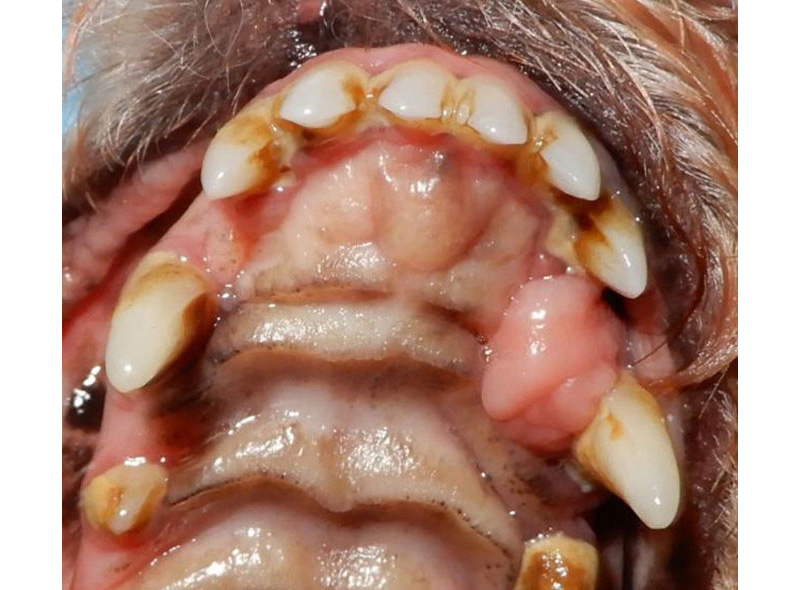

猫の吸収病巣

歯頸部の骨が虫食い状に溶けています。見た目は、一見歯周病の歯に見えますが、歯冠部のみが動揺し、根っこは残存したままとなります。この状態では、根っこの神経が露出したままとなり、痛みや炎症は治りません。